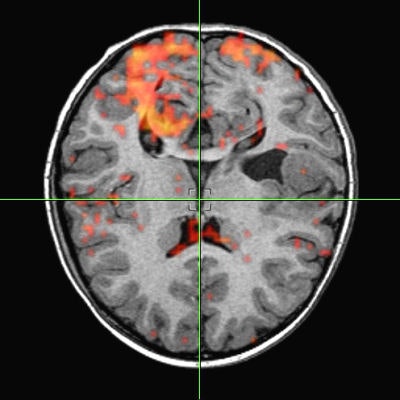

Tomographic examination of pathologies is currently performed by slice-based visual inspection despite the volumetric nature of the anatomical components, tumors/lesions, and imaging modalities. The reason for this could be the radiologist's 2D-based training for distinguishing between normal and abnormal tissue. The introduction of 3D imaging and augmented reality has prompted a huge interest in the utilization of such technology. Virtual endoscopic systems based on perspective rendering have been developed to allow the physician to "fly through" the patient's anatomy. Using such methods, the physician can reduce the opacity of certain tissues (such as the brain) to look at the internal structures (see figure 5, below).

To augment the physician's vision during diagnostics and the examination process, numerous visualization and fusion algorithms have been developed. However, there seems to be a considerable discrepancy between information presented as a volumetric image and the information accessible by the clinical analysis of 2D images. These methods also lack standards, from image acquisition to reconstruction. The lack of adequate and reliable segmentation -- visualization standards, statistical analysis, and the training associated with them -- are main factors in the slow progress of the effective utilization of 3D diagnostics in modern clinical practice.